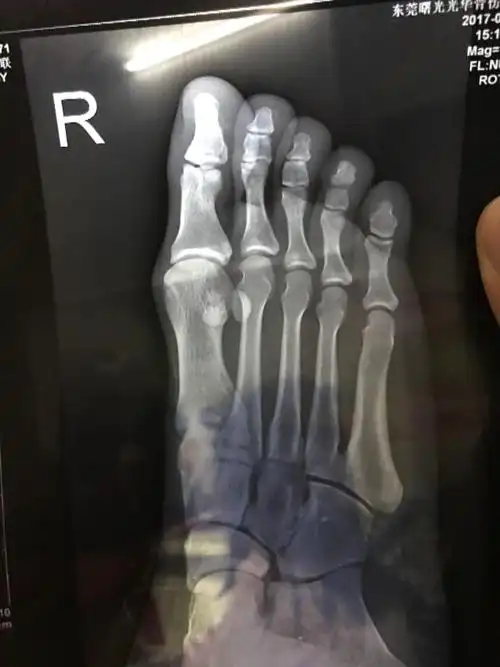

请教下是第四脚趾骨骨折吗?